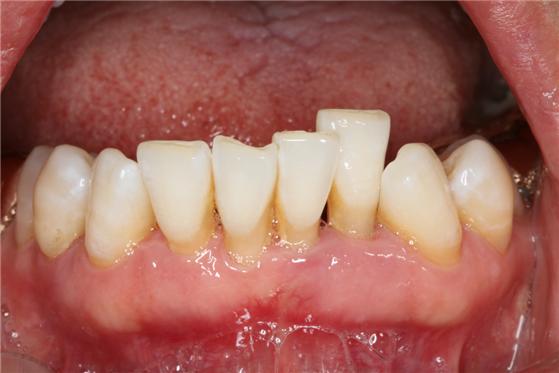

치료법으로는 가장 중요한 것은 올바른 양치질 습관을 바로잡는 것이다. 하지만 잇몸 퇴축이 진행 중일 경우 그 원인이 염증에 있다면 치주치료를 통해 불량한 구강 위생 상태를 해결할 수 있지만, 한번 퇴축된 잇몸은 쉽게 회복되지 않아 잇몸 퇴축 부위, 잇몸 형태, 퇴축 정도에 따라 잇몸성형술과 잇몸 이식술 등으로 치료할 수 있다. 잇몸 이식술은 구개(입천장) 측에서 충분한 양의 결합조직 이식 편을 채취해 퇴축 부위에 덮는 방식으로 진행한다. 치료를 통해 노출된 치아 뿌리를 덮고 잇몸의 높이와 부피를 회복할 수 있다. 이에 앞서, 치주질환으로 인해 전반적인 치조골 소실과 치은퇴축 양상이 관찰되는 경우에는 철저한 치주치료로 더 이상의 퇴축을 방지하는 것이 필수적이다.

잇몸이식술을 통해 노출된 치근면을 덮기 전(왼쪽)과 치료 후 모습(오른쪽)